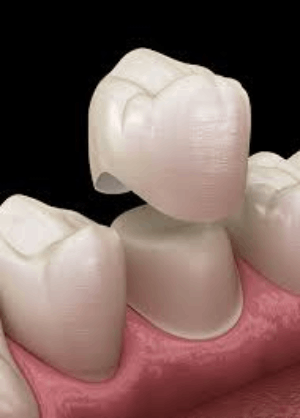

CEREC - same day crown

CEREC (Chairside Economical Restoration of Esthetic Ceramics) is a CAD/CAM technology that allows dentists to design, create, and place a custom, high-quality ceramic crown in a single appointment. It eliminates the need for messy traditional impressions, temporary crowns, and second visits by milling the restoration on-site in under two hours